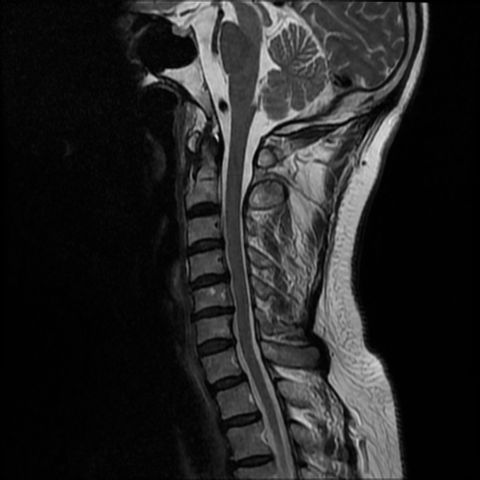

我們中心的影像

2022 年新型號, 影像更清晰

磁力共振頸椎

上肢麻痺、無力及難以控制特定肌肉、頸椎退化等